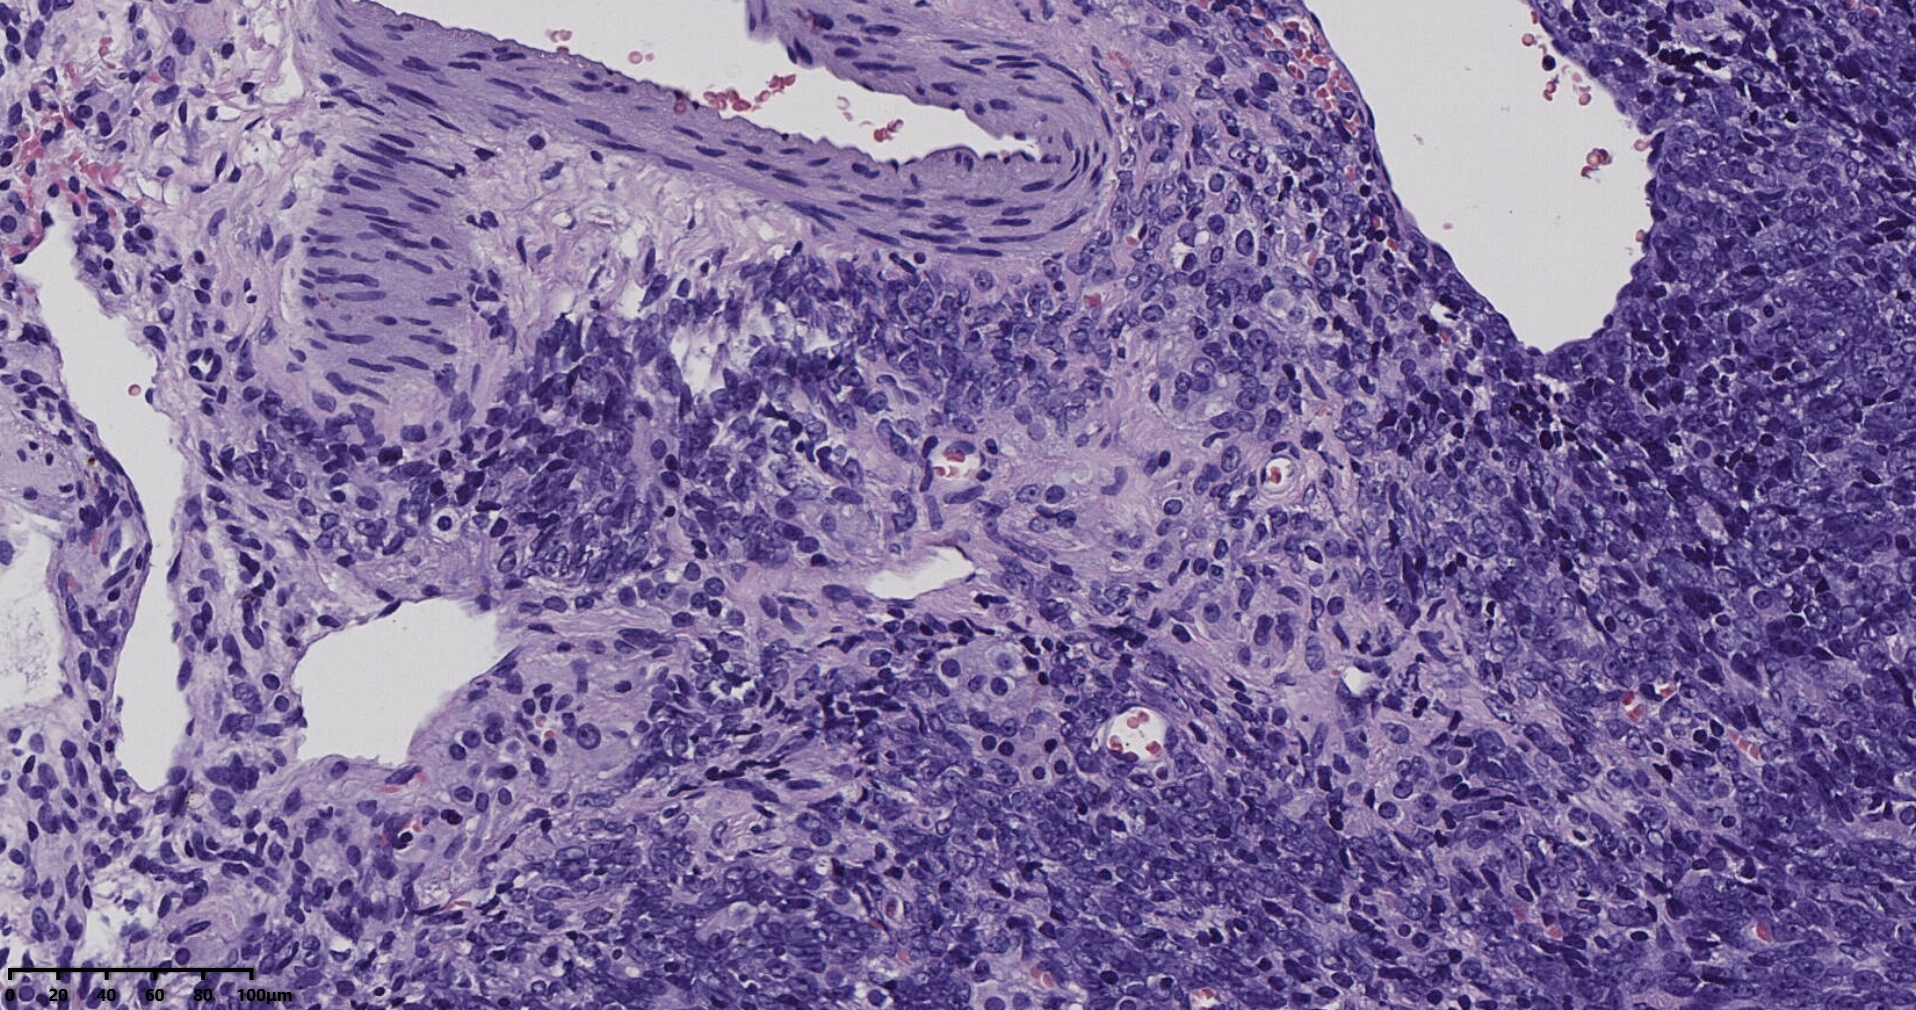

冰冻切片取两块实性区组织,其中1块可见梭形细胞为主,另一块似上皮样细胞,细胞丰富密集。

术中考虑卵巢性索间质来源肿瘤,待石蜡及免疫组化。

常规切片

考虑颗粒细胞瘤。